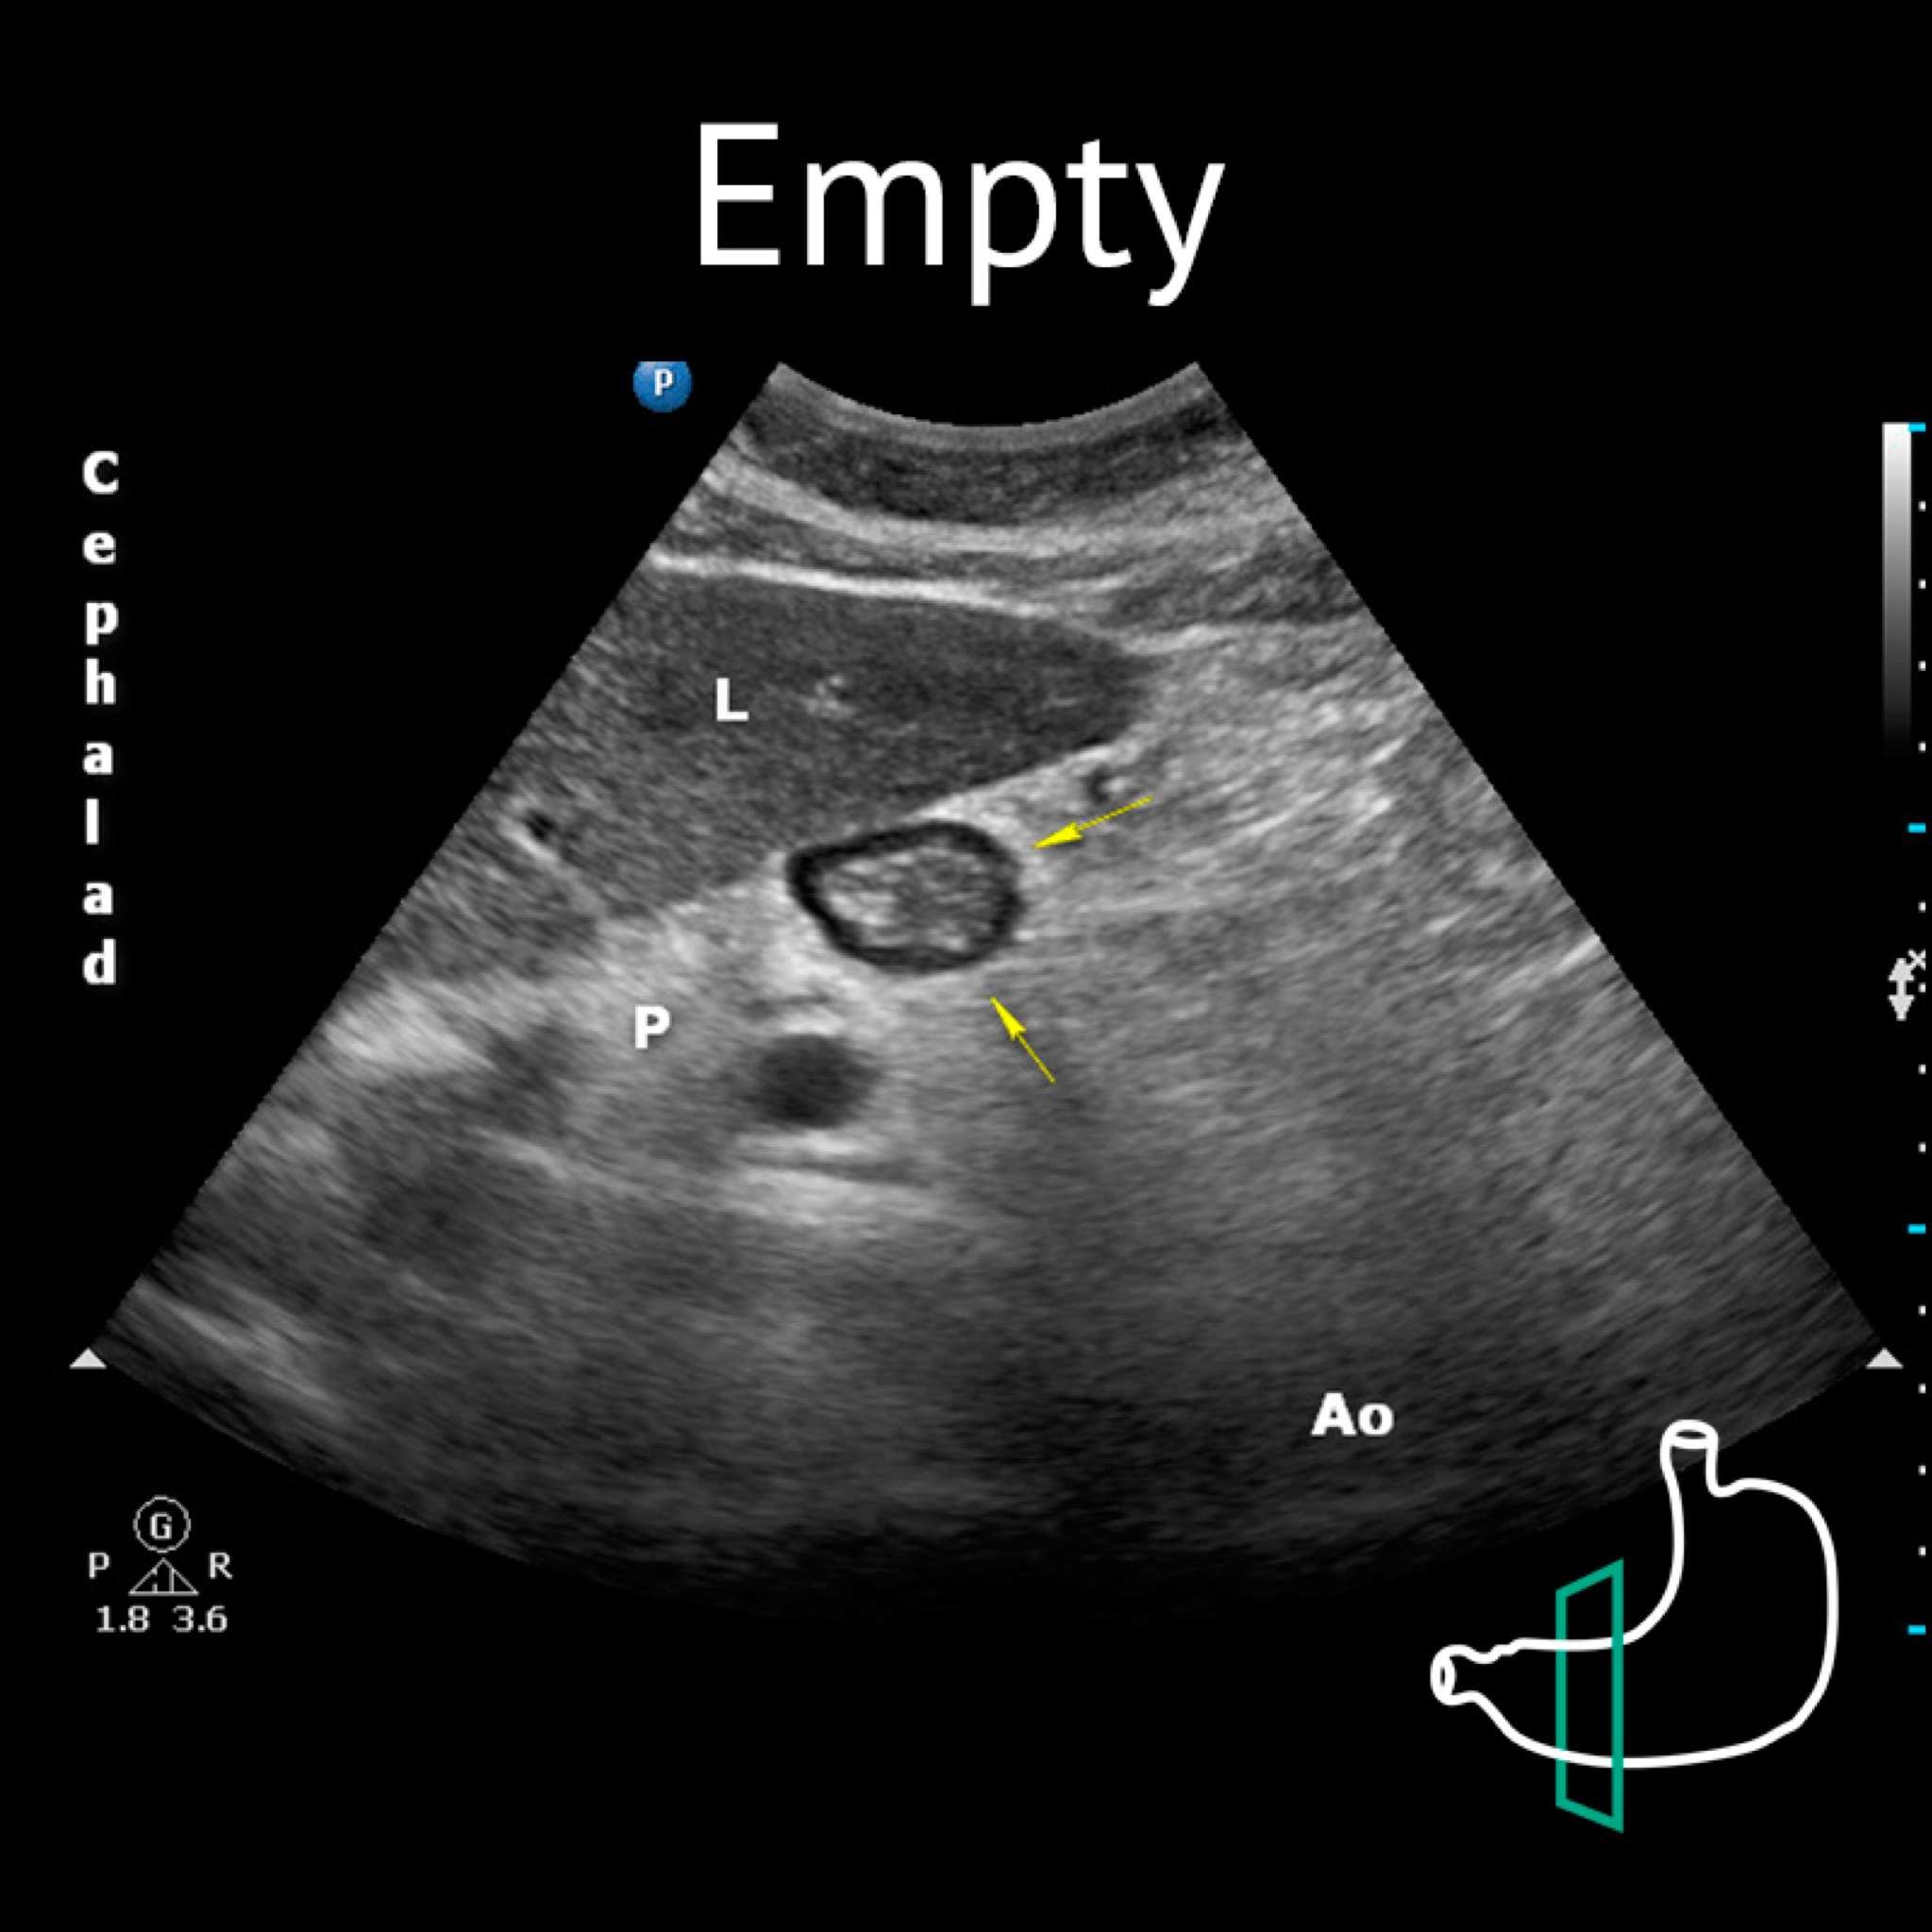

Ao: aorta; L: liver; P: pancreas; Yellow arrows: antrum